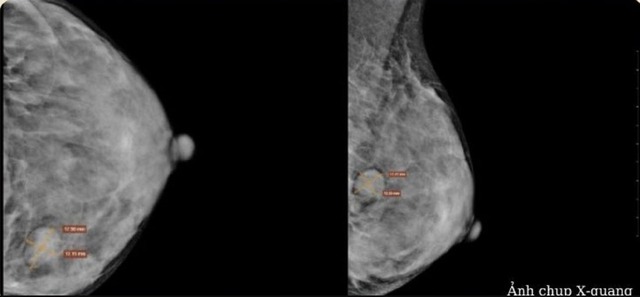

Hình ảnh siêu âm khối u xơ vú lành tính thường gặp ở phụ nữ trẻ.